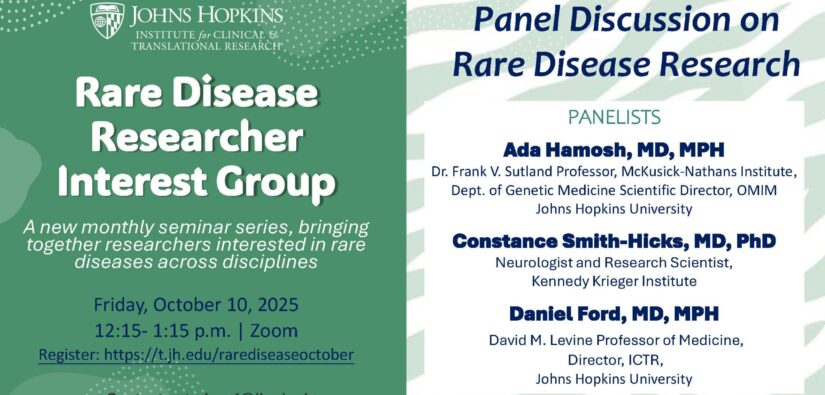

Events Calendar